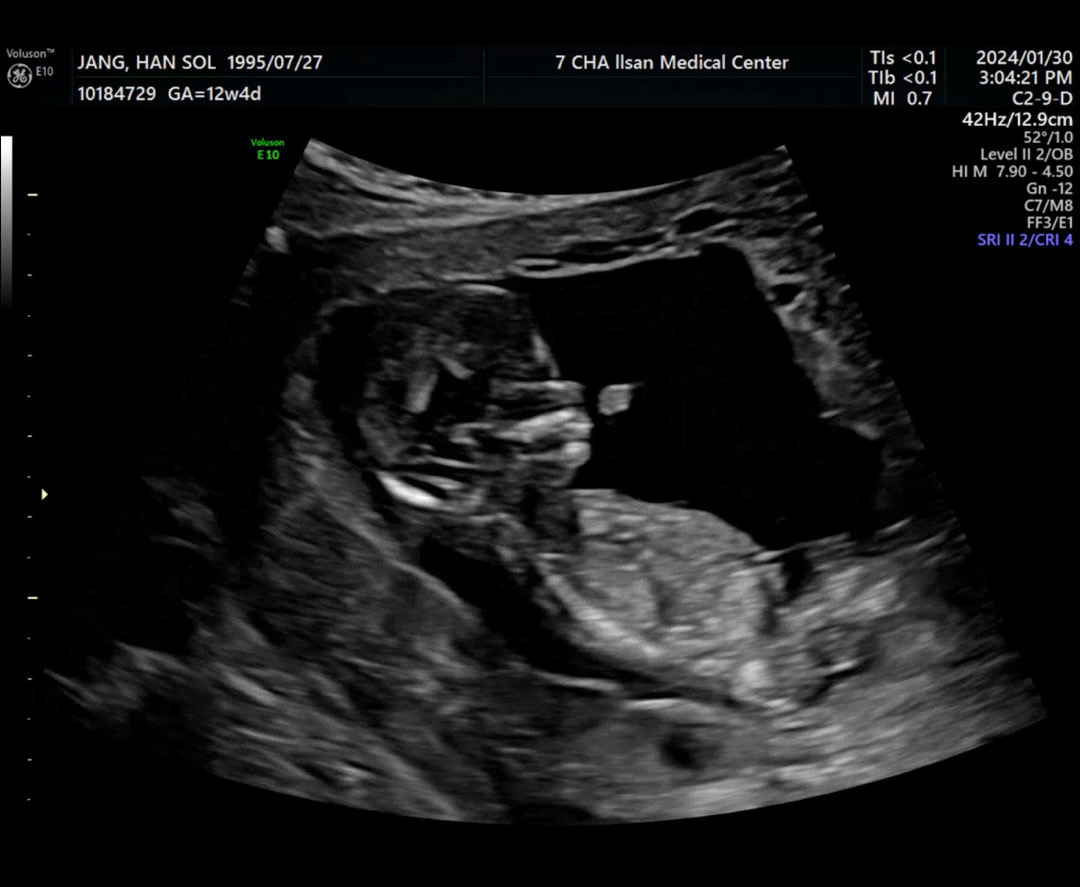

12주차 각도법 봐주세요!

초음파 보다가 탯줄을 다른거로 착각했네요ㅎㅎ 각도법으로 보기에 어떠세요? 성별 너무 궁금하네요!!